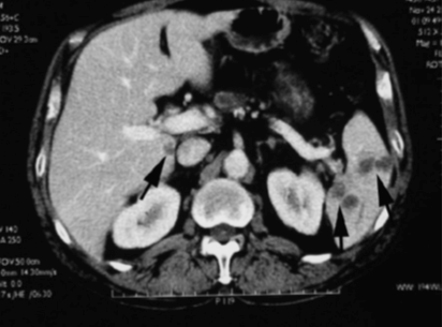

【画像所見まとめ】

• 右頸部に多発する嚢胞性(または壊死性)病変、リンパ節腫大

• 脾多発腫瘤、脾門部多発リンパ節腫大

【1年前の画像】